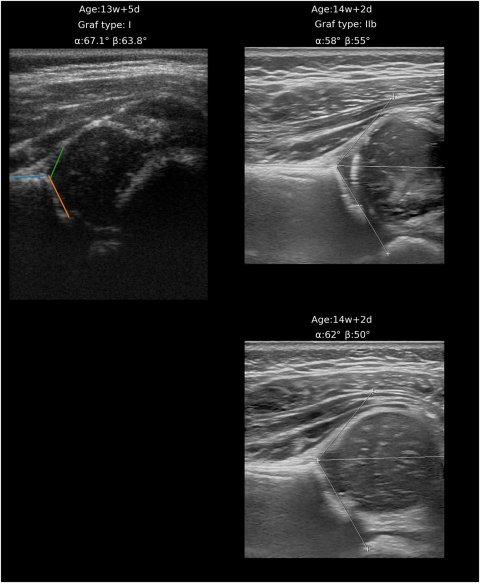

Image source: Verhoeven MMR, Klein WM, De Monye W et al., Computer Methods and Programs in Biomedicine 2025 (CC BY 4.0)

Traditionally, training a sonographer to perform hip ultrasounds takes several months, making the implementation of ultrasound at CHC centers impractical. Researchers from Radboudumc and JGZ Kennemerland have shown that CHC physicians can be trained in just one hour to perform an AI-assisted ultrasound at the CHC center. Consequently, introduction of ultrasound at the CHC center could improve the specificity of the screening program and reduce the number of unnecessary referrals.

In this study, two CHC physicians scanned a total of 105 infants at the CHC center. The AI application’s results were evaluated by two trained radiologists, showing that 56% of infants without DDH could be correctly identified. This means that only 3.5 infants need to be referred to the hospital for an ultrasound to detect one infant with DDH. Therefore, the specificity improves to 92%.